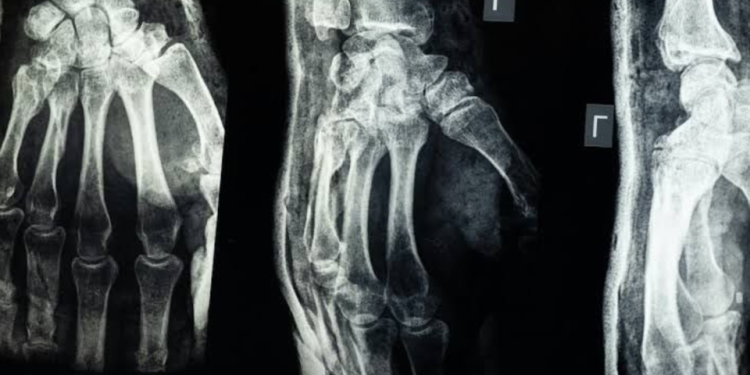

China.- Un grupo de investigadores de la Universidad de Zhejiang, en China, presentó Bone 02, un gel adhesivo revolucionario que promete cambiar la forma en que se tratan las fracturas óseas. El material puede unir huesos rotos en apenas tres minutos, sin necesidad de cirugías invasivas ni implantes metálicos.

Bone 02 ya fue probado en más de 150 pacientes, mostrando gran resistencia, rápida absorción y reduciendo riesgos como infecciones y complicaciones posquirúrgicas. A medida que el hueso se regenera, el gel se degrada de forma natural, evitando la necesidad de una segunda operación.